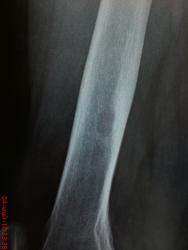

Здравствйте , коллеги! женщина, лет 40 , жалобы на хруст в левом коленном сустае при ходьбе. для сравнения сделали правый - и вот какая находка в дистальной трети правой бедренной кости (болит левый коленный сустав). Никаких жалоб на левую ногу нет. единственное , что помнит- была какая-то операция , со слов на м.тканях, как раз в этой области лет 10 назад - "был гной". связанно ли это с находкой или нет не знаю. Вижу 2 очага со склеротичесим ободком без клиники, надкостница и м.ткани вроде не реагируют. как вы думаете , что это может быть?

Скорее всего это ассимилированные периостальные наслоения, остеосклероз. Если так, то вероятен залеченный остеомиелит.

Очень смутила минералопения в метафизе, причем выраженная... и деструкция...

Жалоб никаких. признаки остеопении быть может из-за обработки снимков(подыграл светом и тенью). на р-граммах коленных суставов в 2-х пр-ях - структура костей , кроме этих очагов разряжения , вполне нормальная...

все доброкачественное из образований - эпиметафиз, для злого - нужна клиника , отсутствие склероза. может Фиброзный кортикальный дефект?

Это ни краевой кортикальный дефект для которого характерно наличие кортикального склероза с фестончатыми краями, ограниченного замыкательной пластинкой. В данном случае имеется разряжение костной ткани ближе к овоидной форме, края четко визуализируются уплотнены, это кистовидное просветление, надо отметить режим без особенности,  даже мягкие ткани визуализируются, что при жестком снимке не было бы, а значит и остеопороз явно на лицо, да и с учетом возраста, признаки умеренного остеопороза есть. Если смущает наличие кисты, можите провести рентген-контроль через 6 месяцев, ни чего злокачественного нет и это самое главное.

Киста и не чего большего, на фоне чего остается только догадываться, а замыкательная пластинка это "кортикал".

Написал бы Последствия перенесённого остиомиелита. Костная киста. Рентген контроль через  6 мес.

А я вижу очаг фиброзной дисплазии. А утолщение кортикального слоя - возможно, просто утолщение кортикального слоя после перенесенного заболевания мягких тканей.